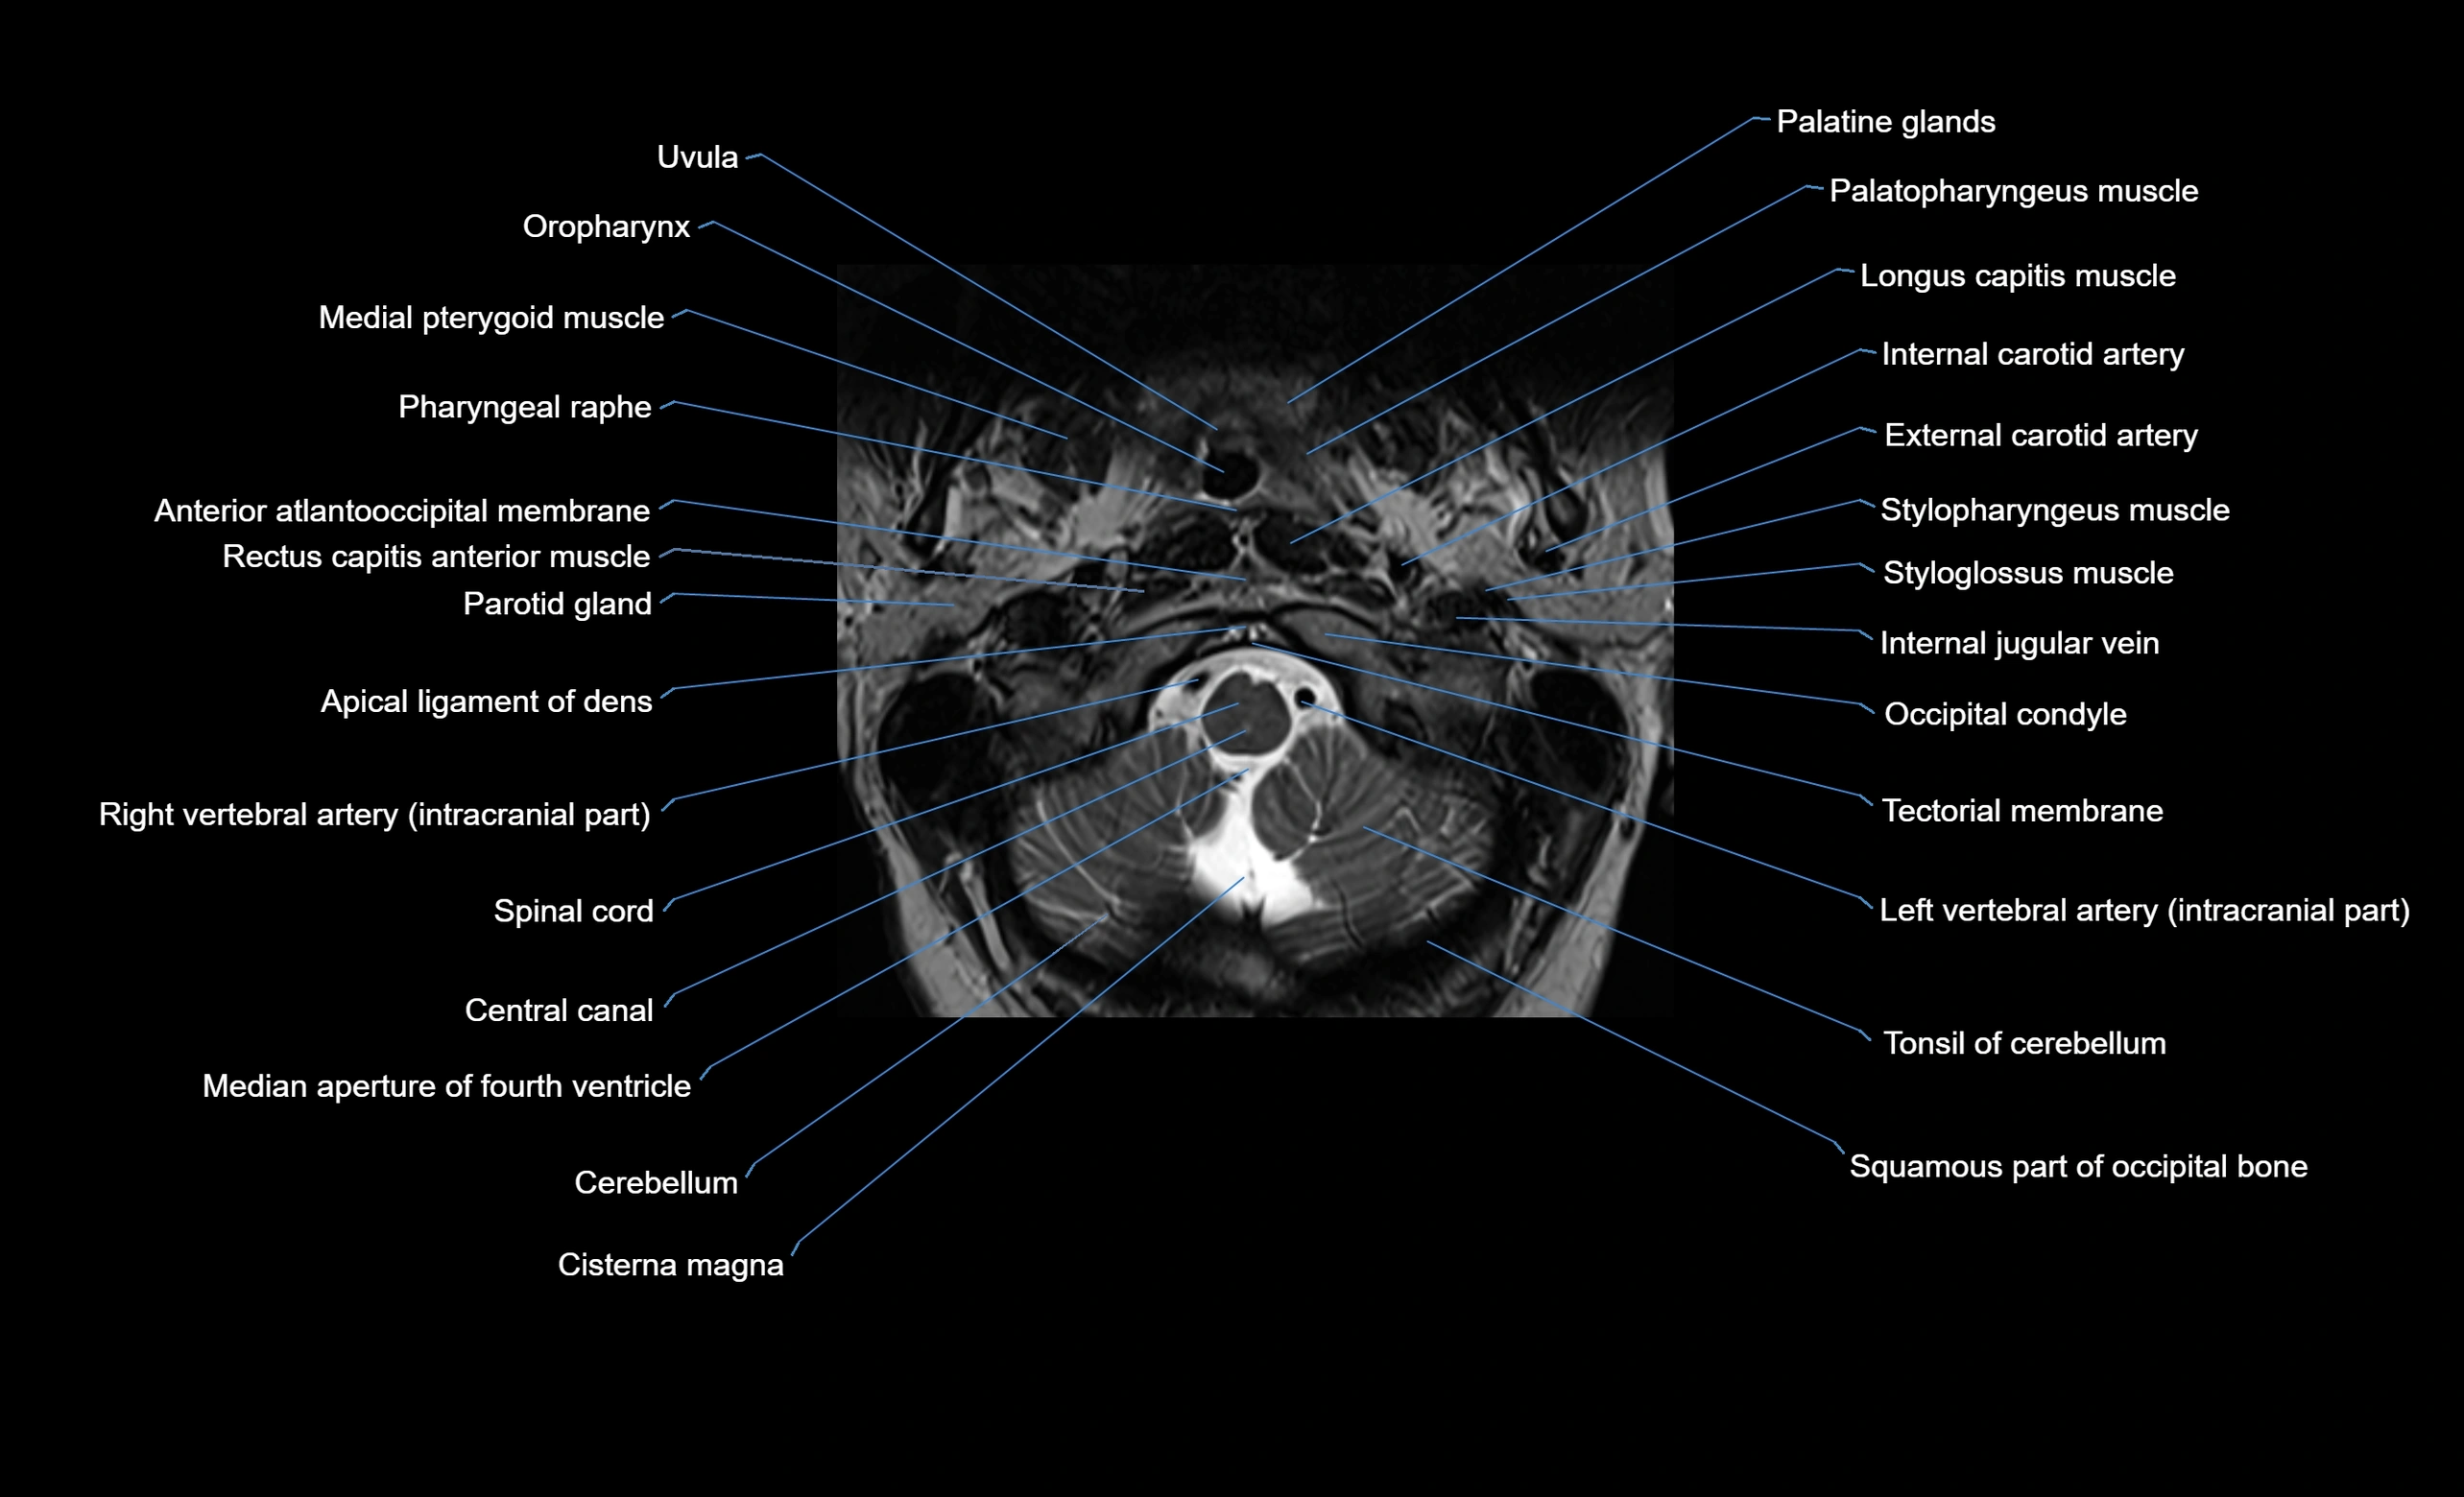

MRI image

image